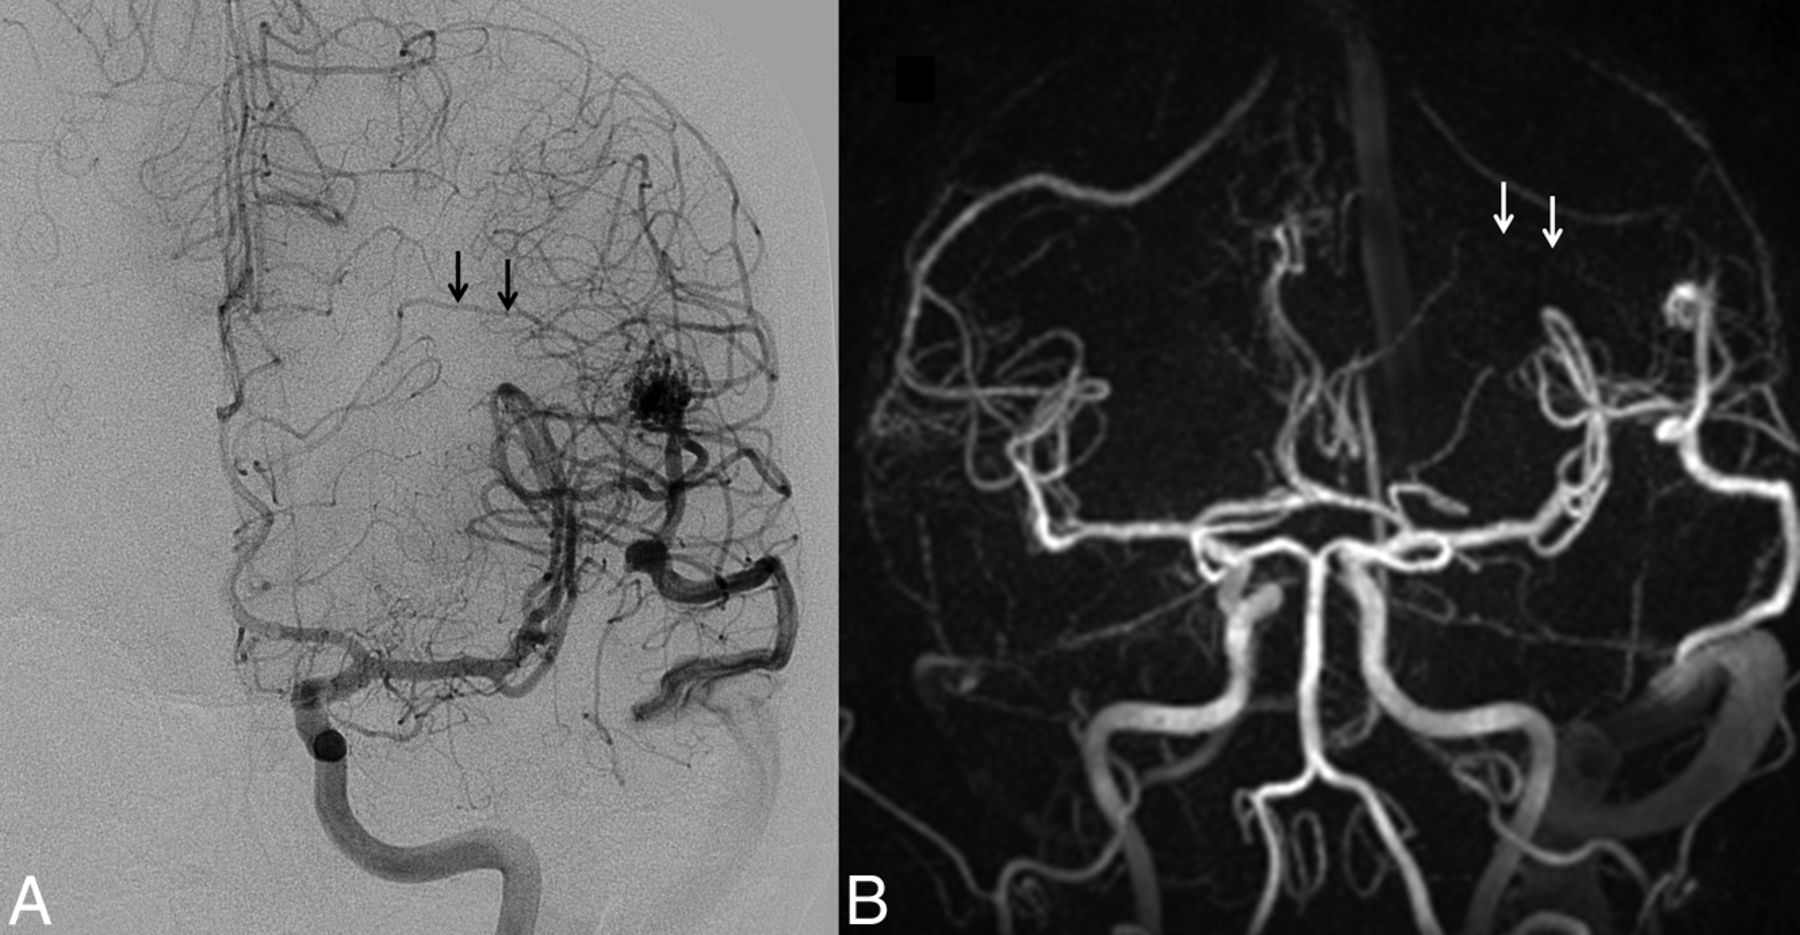

Left posterior frontal AVM. A, The DSA examination demonstrates a small deep medullary vein (arrows), which drains into the straight sinus. The AVM nidus was in close proximity to the Broca area and was scored as Spetzler-Martin grade III. B, Coronal HYPRFlow late arterial phase image with poor delineation of the deep medullary vein (arrows), resulting in incorrect classification of the AVM as Spetzler-Martin grade II.

The Spetzler-Martin grades and number of patients in each category based on DSA were grade I (n = 2), grade II (n = 4), grade III (n = 3), grade IV (n = 3), and grade V (n = 2) (Figs 2⇑–4). There was 1 instance in which very small deep medullary draining veins were not identified on the HYPRFlow examination, resulting in disagreement with the DSA Spetzler-Martin grade (Fig 5); otherwise HYPRFlow and DSA were in concordance.